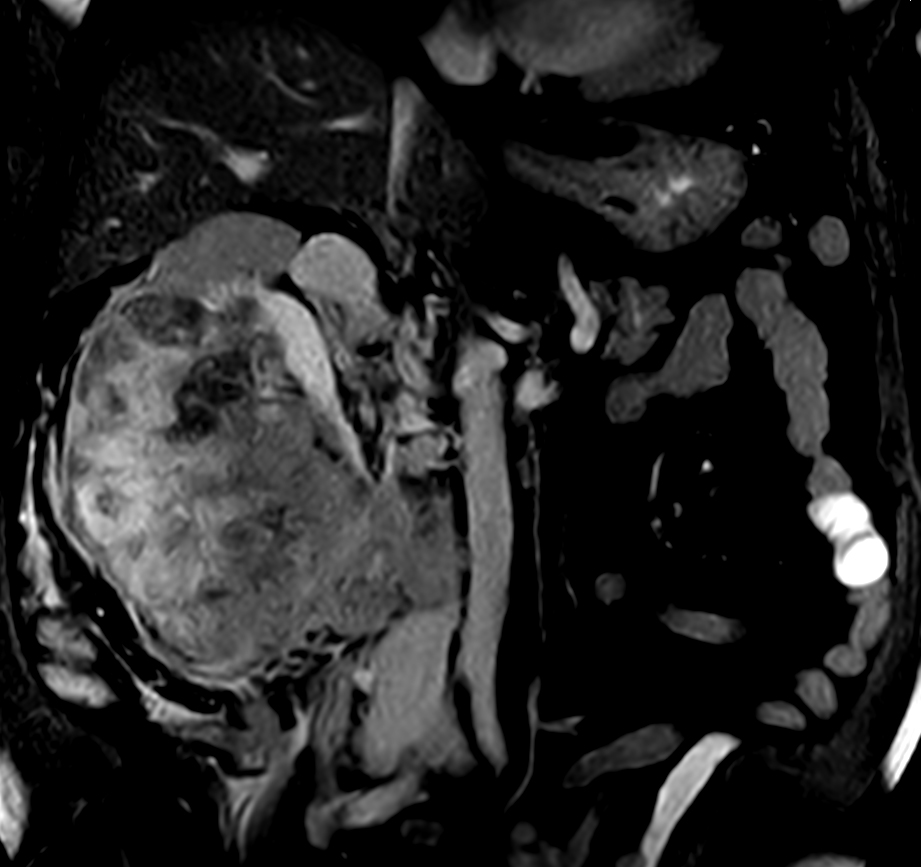

Patient with kidney tumor. ExamCard includes Compressed SENSE to shorten the breath hold time, VitalEye for touchless respiratory sensing, mDIXON XD FFE to acquire up to four image types in one single scan, DWIBS to achieve high contrast between background and lesions and bTRANCE for non-contrast time-resolved imaging.

bTFE - VitalEye Compressed SENSE